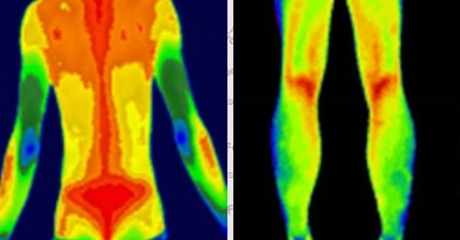

凌晨的急诊室里,医生用一台手持设备扫描患者的左腿——屏幕上显示患处温度比右腿低2.3℃。十分钟后,血管造影证实了深静脉血栓的存在。这台救命的设备正是医用红外热像仪,而它与普通工业热像仪的差异,远比想象中更致命。

自动标注肢体温差>1℃的区域(提示血栓风险)

动态监测糖尿病足微循环变化

案例:北京某三甲医院用其提前7天预警糖尿病患者足部坏死风险

炎症可视化

智能识别类风湿关节炎的“梭形热区”

量化评估强直性脊柱炎进展程度

(插入示意图:脊柱炎症热图 – 红色热区与MRI病灶位置完全吻合)

乳腺癌:患侧乳头温度升高0.5-2℃

甲状腺癌:肿瘤区域呈现“热岛效应”